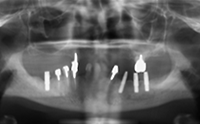

図❷ 初診時のパノラマX線写真

画像所見:パノラマX線写真では左側臼歯部にインプラントが埋入されていたが、周囲の骨の吸収像や骨の硬化像は認めなかった(図❷)。造影CTでは左側下顎体部尾側から骨内側に軟部腫瘤があり、腫瘤は造影効果を認めた(図❸)。内部は均一で、境界は比較的明瞭であった。また、膿瘍を疑う液貯留は認めなかった。PET検査では、腫瘤に一致してSUVmax=17.6のFDGの集積を認めた。